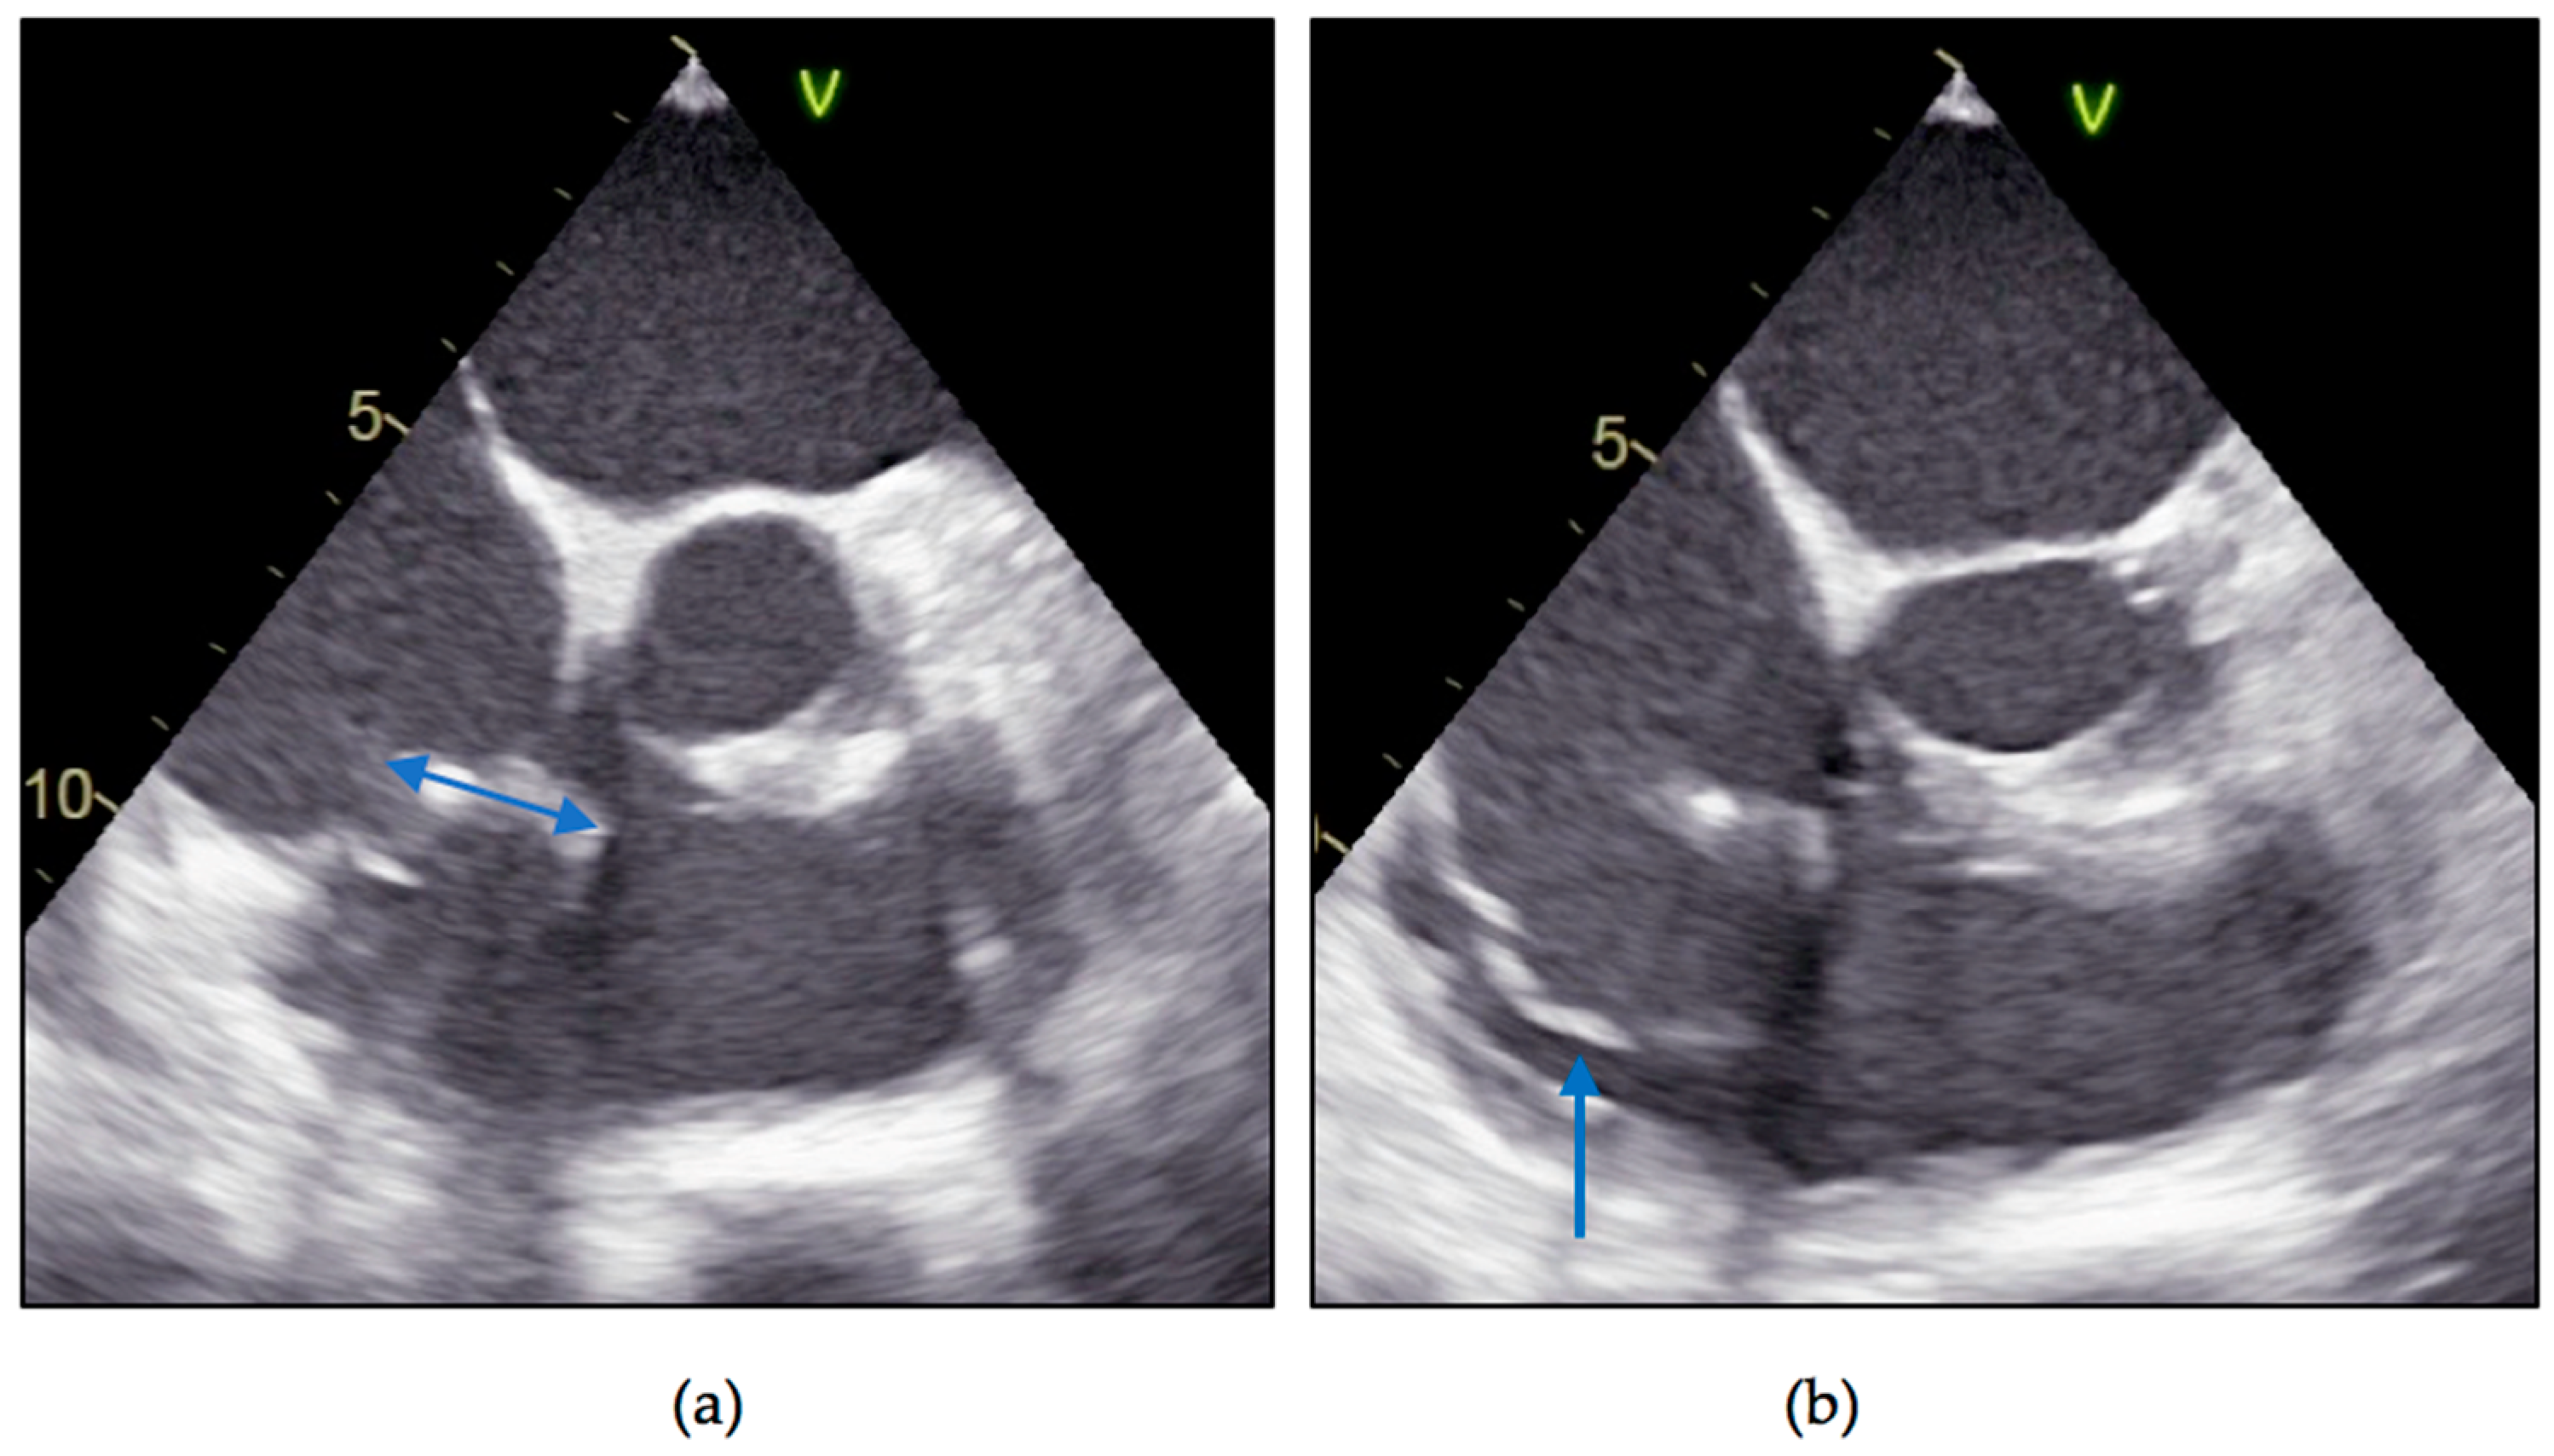

2. Case Report